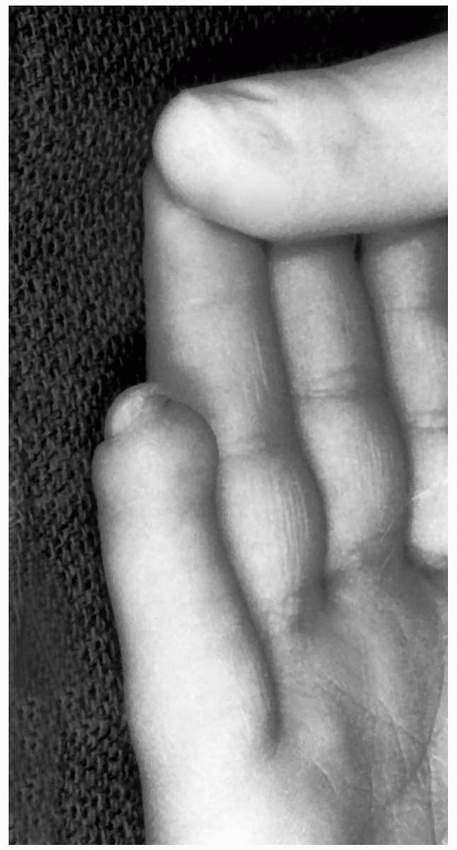

![]() |

FIGURE 8-22 A. A 13-year-old boy sustained an open S-H type II fracture. B. The wound was cleansed, and acceptable alignment was obtained with closed reduction.